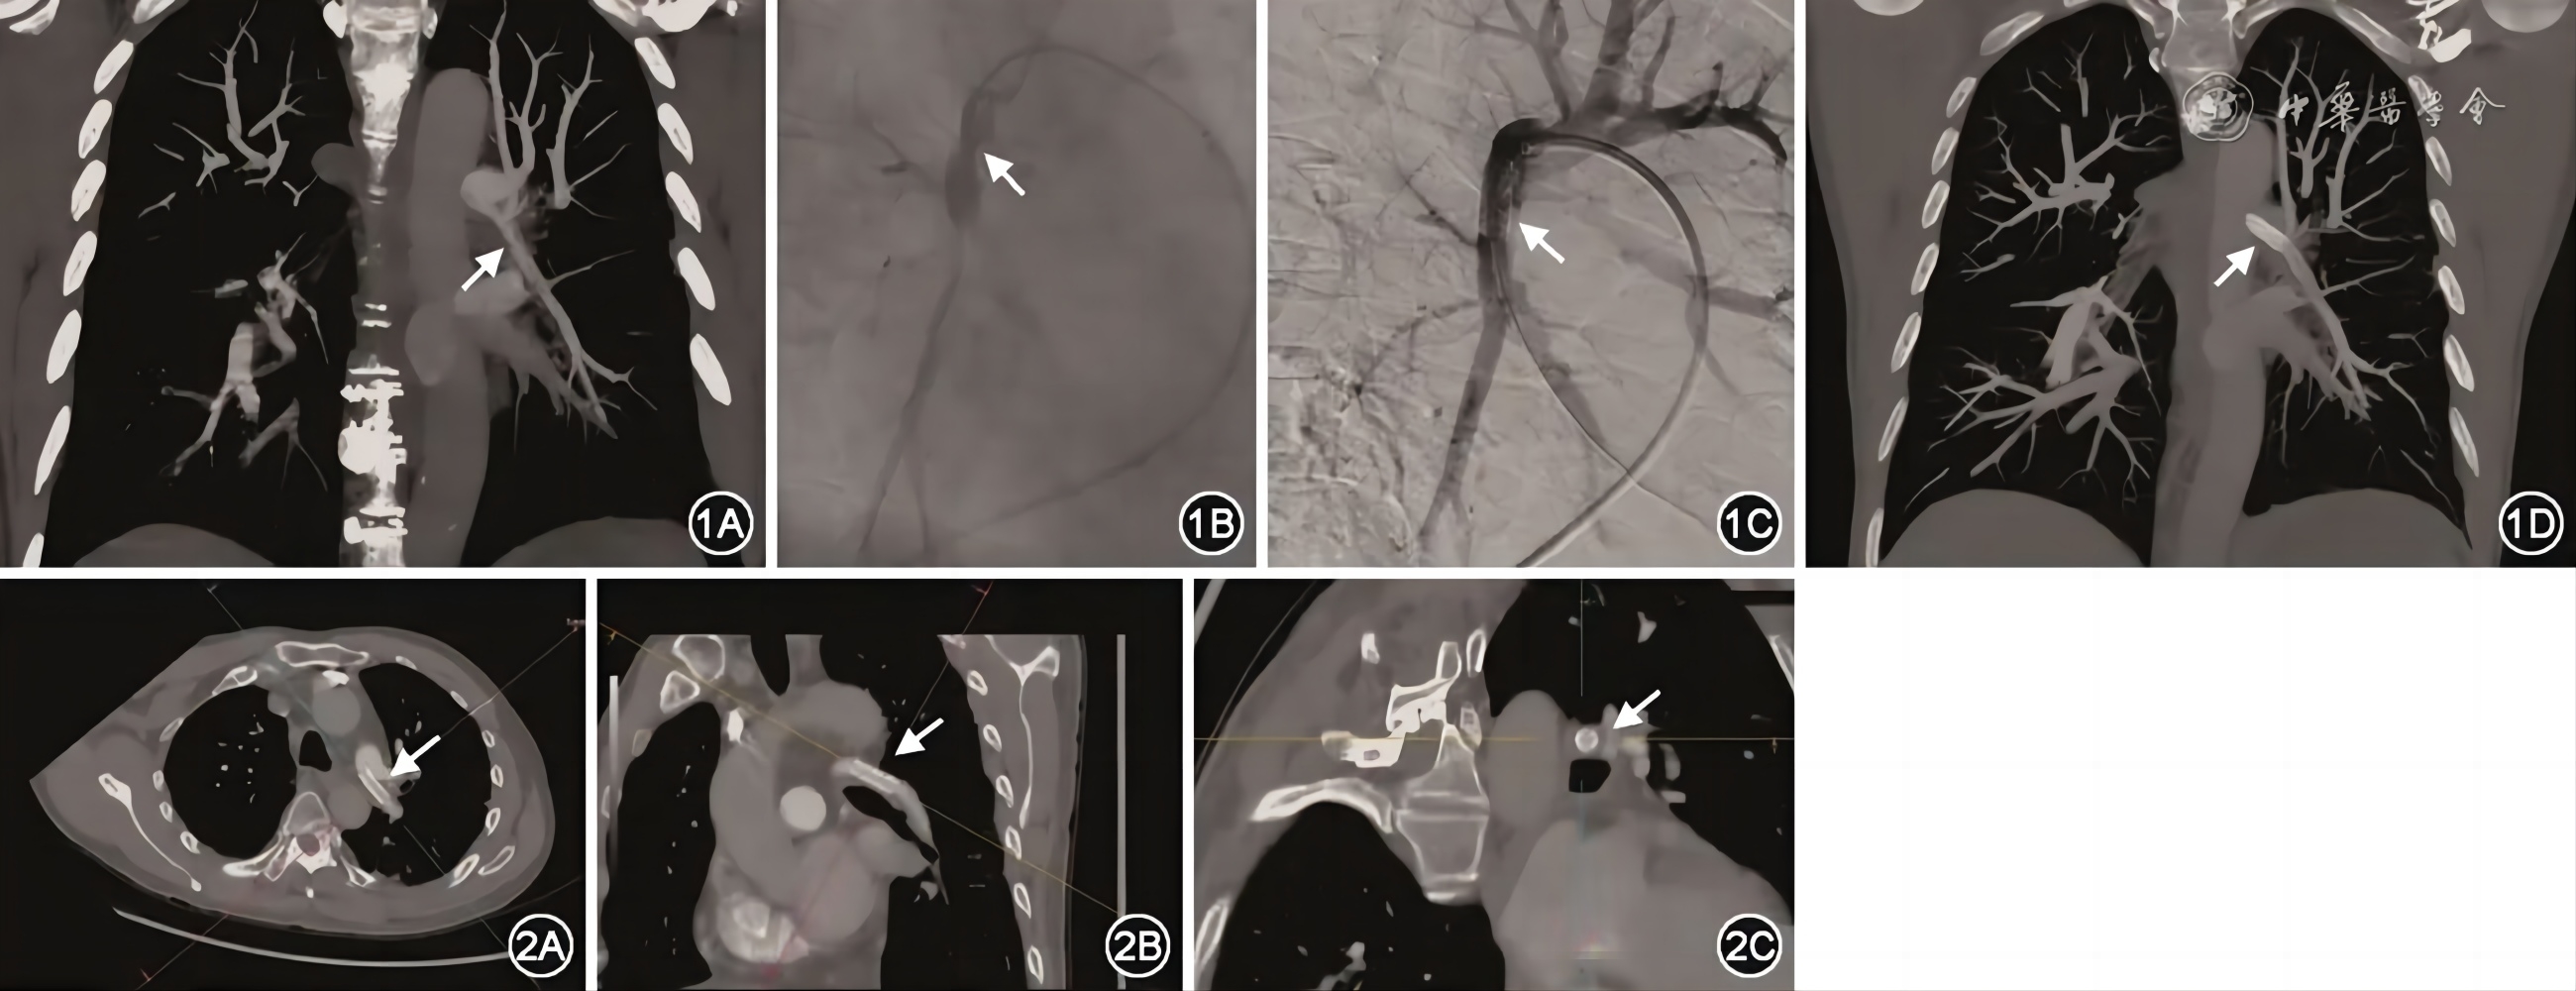

入院后体格检查:体温36.5 ℃,脉搏92次/min,呼吸频率20次/min,血压139/90 mmHg(1 mmHg=0.133 kPa),双肺呼吸音清,未闻及干湿性啰音,心率92次/min,律齐,P2>A2,各瓣膜区未闻及杂音,腹软,双下肢无水肿。辅助检查:心脏彩超示:三尖瓣反流,估测肺动脉收缩压58 mmHg。CT肺动脉造影(CTPA)示:两侧肺动脉多发段及以下分支慢性栓塞并管腔狭窄、部分分支闭塞,以右下肺动脉为著(图1A)。双下肢静脉彩超及腹部彩超未见异常声像。血浆D-二聚体 555 ng/ml;氨基末端B型利钠肽前体(NT-proBNP)34.32 ng/L;进一步查肌钙蛋白、易栓症、同型半胱氨酸、抗核抗体谱、血管炎筛查均未见异常。右心导管提示:毛细血管前性肺动脉高压。肺动脉造影显示:左肺动脉多发狭窄,血流缓慢。患者诊断为“慢性血栓栓塞性肺动脉高压”。评估患者状况,考虑患者肺血栓病灶主要位于外周肺动脉,PEA术获益可能性不高,选择BPA治疗。2021年12月9日行第1次BPA(表1),术后患者气促症状好转出院。2022年4月12日患者返院行第2次BPA,术中造影示左下肺动脉基底干狭窄明显,使用导丝通过狭窄病变至血管远端,测量狭窄近端压力38/12/23 mmHg,远端压力15/7/11 mmHg,压差明显。测量狭窄管腔大小8 mm,依次使用Boston Scientific 6.0 mm×30 mm、7.0 mm×30 mm及8.0 mm×30 mm尺寸的球囊导管,逐渐扩张病变,扩张压力为8~10 atm,每次扩张时间10~15 s(球囊工作压范围6~14 atm)。扩张后复查造影狭窄病变仍呈束腰状(图1B),球囊扩张后狭窄近端压力35/12/22 mmHg,远端压力17/7/12 mmHg,近端与远端压力差明显,提示球囊扩张效果不佳,决定行肺动脉支架植入术。根据肺动脉造影结果,将1枚Boston Scientific 8.0 mm×27 mm支架沿导管放置于左下肺动脉基底干,造影确认支架可覆盖狭窄范围后,8 atm压力扩张球囊释放支架(支架球囊工作压范围6~12 atm),支架植入后复查造影示支架膨胀理想,支架未见狭窄,选用Boston Scientific 8.0 mm×30 mm的球囊导管在支架近端再次扩张压力10 atm(球囊工作压范围6~14 atm)(图1C)。复测支架近端压力35/13/22 mmHg,支架远端压力30/11/20 mmHg,压差明显改善(表1)。手术后复查右心导管肺动脉压力明显降低,平均肺动脉压力正常范围(表1)。术后患者觉活动后气促较前明显改善。出院予拜阿司匹林100 mg,1次/d抗血小板和利伐沙班20 mg,1次/d抗凝治疗。拜阿司匹林100 mg,1次/d使用3个月后停用,持续利伐沙班20 mg,1次/d抗凝治疗。术后随访患者症状明显改善。

图1 例1患者影像结果:图1A为患者CTPA冠状位,支架植入前CTPA图像,左下肺动脉基底干血管明显狭窄(箭头所示),图1B为左下肺动脉基底干使用球囊扩张治疗后造影复查,远端血管显影欠佳(箭头所示),图1C为支架植入后造影,支架膨胀良好,远端血管血流通畅(箭头所示),图1D为患者支架植入后CTPA图像,可见左下肺动脉基底干植入Boston Scientific 8.0 mm×27 mm支架(箭头所示)

图2 例1患者肺动脉支架植入术后复查CTPA清晰显示支架位置及全貌,图2A、B显示支架长轴(箭头所示),图2C显示支架横截面(箭头所示)

2023年4月4日(1年后)患者返院复查,CTPA示:左下肺动脉支架植入术后改变,支架通畅(图1D,图2)。行右心导管检查+肺动脉造影检查可见:肺动脉压力正常范围(表1);左下肺动脉造影血流通畅,支架内无明显狭窄。